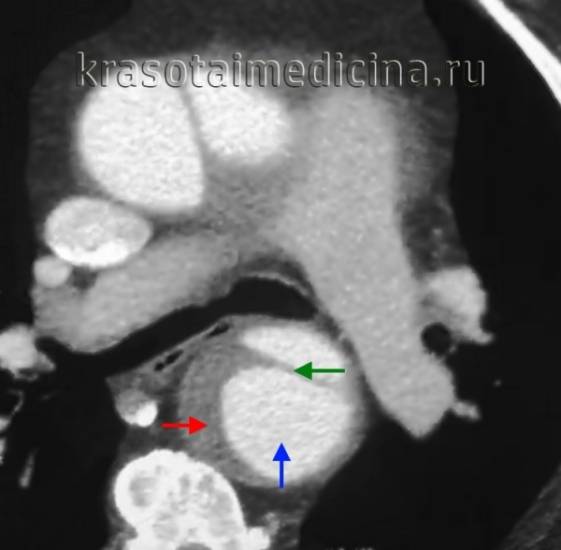

- Томография. Проведение КТ и МРТ при расслаивающей аневризме аорты требует, чтобы состояние пациента было стабильным для транспортировки и выполнения процедуры. КТ используется для выявления интрамуральной гематомы и прорастания атеросклеротических язв в грудной части аорты. МРТ позволяет без применения внутривенного контрастирования точно определить место разрыва интимы, направление расслоения в ложном канале, оценить вовлеченность основных ветвей аорты и состояние аортального клапана.